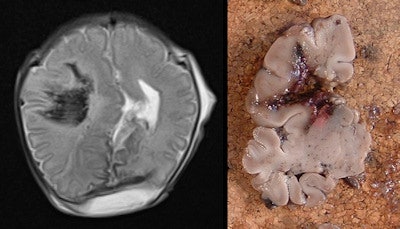

For one, the fetal and neonatal brain is relatively poorly myelinated with greater water content, and, thus, is friable and requires prolonged fixation in formalin prior to sectioning (which may take up to three weeks) causing a delay for funeral proceedings. Also, changes following death or maceration and cell breakdown may render histopathological examination uninformative. And in some situations, detailed examination of the intricate connections and anatomical structure of the brain and spinal cord is best done with the brain in situ, particularly for posterior fossa lesions.

MRI is a particularly good, noninvasive, high spatial resolution exam that gives excellent image contrast between cerebrospinal fluid and brain tissue, thus providing distinct anatomical details. Postmortem MRI, when used in conjunction with other ancillary investigations, has recently been shown to have a high diagnostic accuracy rate for cause of death or main diagnosis compared with traditional autopsy in fetuses, stillbirths, and children.

Formal neuropathological examination was nondiagnostic due to maceration/cell breakdown in 16% of fetuses; of these, cerebral postmortem MRI provided clinically important information in 53%. The sensitivity of postmortem MRI for detecting significant antemortem ischemic injury was only 68% overall.

They go on to write that routine use of postmortem MRI prior to fetal brain autopsy may significantly reduce the nondetection rate for clinically significant pathologies that are difficult to assess, such as posterior fossa malformations.